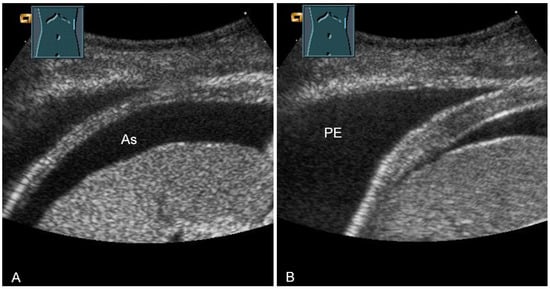

The thickness increase during inspiration was also used as a measure of muscle contraction. In most studies, an increase during inspiration of >20% is considered as normal [55] (Figure 31).

Figure 31.

Representation of diaphragm thickness in expiration (A) and inspiration (B) in pleural effusion (PE) and ascites (As).